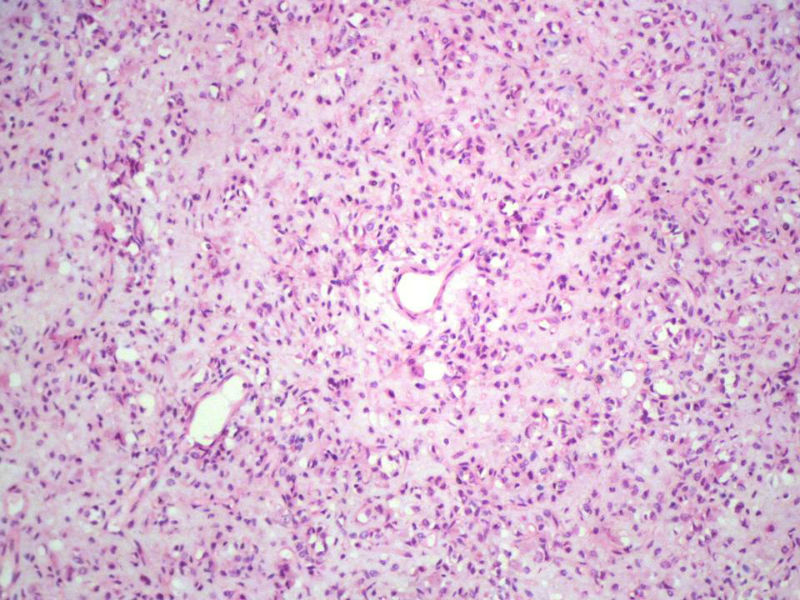

男,27岁,右股骨上段皮下肿物1年余,无明显疼痛,检查肿物明显隆起于皮下,边界清楚,手术完整切除肿物。肉眼,肿物6X6X5厘米,外观多结节状,似有包膜,切面灰白色,质韧。

特别提示:镜下核分裂3-4/HP.